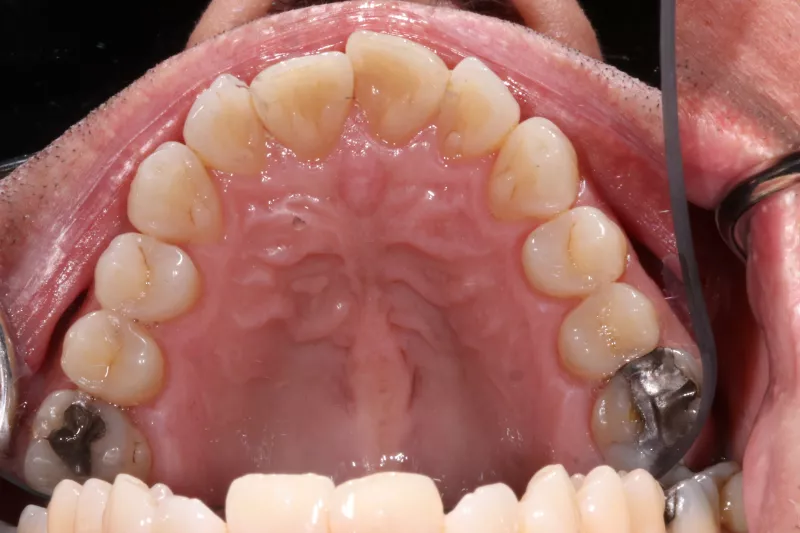

Upper Arch Invisalign to fix overcrowded teeth